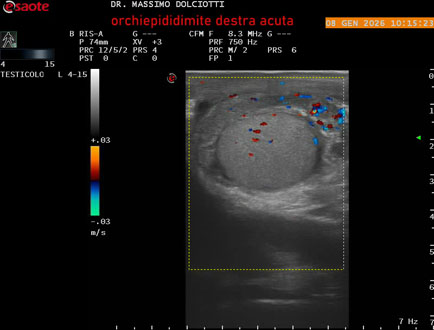

Data inserimento: 08/01/2026

Ecografia del: 08/01/2026

Strumento: Esaote MyLab Eight

Sonda: Lineare Multifrequenza 4-15 MHz

Età Paziente: M 74 anni

Motivazione dell'esame: da 3 giorni dolore e tumefazione al testicolo destro.

Commento all'esame: le immagini ed il video documentano il didimo destro, aumentato di volume, con incremento della vascolarizzazione; aumentato di volume e di vascolarizzazione anche l'epididimo destro, Normale il didimo sin e l'epididimo sinistro, Gli elementi ecografici segnalati orientano per orchiepididimite destra acuta.

Conclusioni: orchiepididimite destra acuta (right acute orchiepididymitis).

Presentazione: Dr. Massimo Dolciotti - Ancona